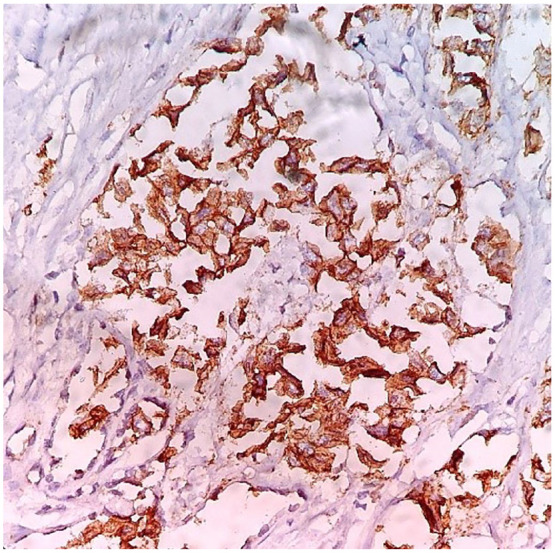

Abstract Image